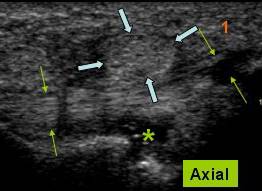

Se traduce ecografic printr-o ingrosare fuziforma a tendonului, centrata de o placa de dezorganizare a fibrelor de colagen care ia un aspect de placa hipoecogena nodulara pe sectiunile axiale si fuziforma pe sectiunile sagitale. Acest nodul se situeaza pe fata profunda a tendonului respectand fibrele superficiale. Prezenta unei vascularizatii de neoformatie reactionala in jurul si pe fata posterioara a nodulului indica cicatrizarea leziunii.

B.-Tendinopatia corporeala Rara, ea se prezinta sub forma unei ingrosari fusiforme corporeale a tendonului centrat de un nodul hipoecogen respectand fibrele superficiele. Semiologia ecografica este similara celei de entezopatie proximala. Una din complicatiile acestei leziuni este